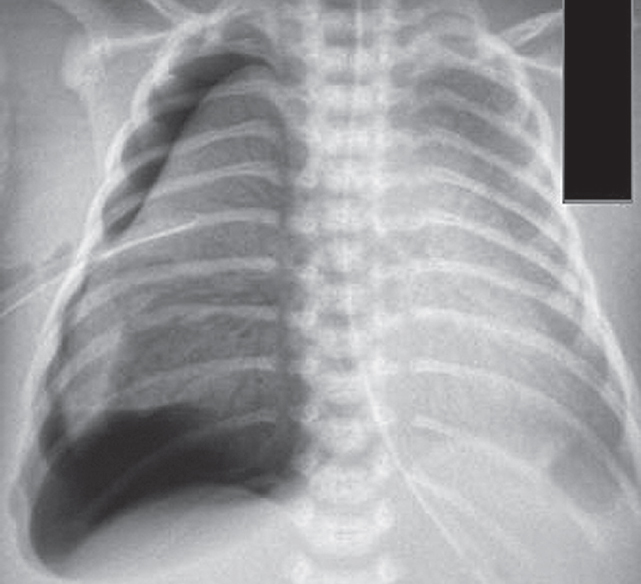

На контрольной рентгенограмме, выполненной на вторые сутки жизни (после введения сурфактанта), сохраняются признаки тяжелого РДС, осложнившегося правосторонним напряженным пневмотораксом (рис. 2), в связи с чем по экстренным показаниям было выполнено дренирование плевральной полости.

Рис. 2. Рентгенограмма органов грудной клетки новорожденного после введения сурфактанта

Fig. 2. Chest X-ray of newborn after surfactant administration